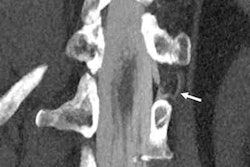

Reference protocol (top) and evaluated protocol (bottom) images in a 74-year-old man with multiple myeloma. Soft-tissue reconstruction is shown (left side; window width, 400; window level, 40), whereas the right column is the bone reconstruction (right side; window width, 3700; window level, 600). A lytic bone lesion in the L3 vertebral body is more conspicuous on the noncontrast-enhanced axial photon-counting CT reconstruction images (bottom; solid arrows) compared with the noncontrast-enhanced axial energy-integrating detector CT reconstruction images (top; dashed arrows). Image and caption courtesy of the RSNA.Whole-body low-dose CT has a mean effective dose that ranges between 4 mSv and 8 mSv, but low-dose images can be noisy. Photon-counting CT shows promise for imaging bone disease caused by multiple myeloma because its smaller detector pixel sizes eliminate the need for the high-spatial-resolution filters that conventional CT requires -- which translates not only to better dose efficiency but also less noise.